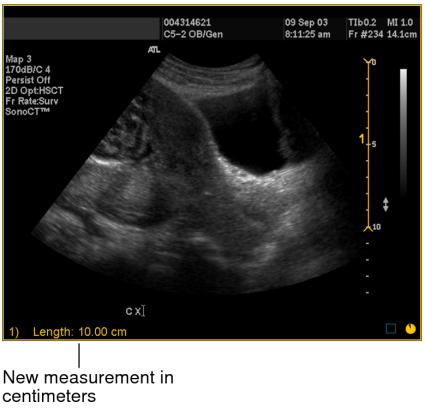

Once you calibrate an image, rulers appear on the image to provide a visual indication of scale.

The image is calibrated and the length of the measurement now appears in centimeters. All subsequent linear, orthogonal, elliptical, and freehand region of interest measurements that you create on the image are calibrated according to this ratio.